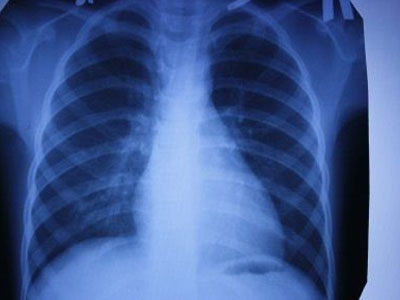

據(jù)我國(guó)大的出國(guó)看病服務(wù)機(jī)構(gòu)厚樸方舟了解,日本科學(xué)家近日宣布,他們成功發(fā)現(xiàn)了一類(lèi)基因,它們的變化具有加速人類(lèi)肺癌細(xì)胞擴(kuò)散的可能性。

科學(xué)家在非吸煙者身上診斷出了這一疾病類(lèi)型。這類(lèi)基因一共有六種。日本癌癥研究中心的專(zhuān)家在研究中得出了這一結(jié)論。他們對(duì)1.8萬(wàn)余人的醫(yī)療數(shù)據(jù)進(jìn)行研究,研究參與者中既有健康人群,也有癌癥患者。

專(zhuān)家指出,這些基因主要在發(fā)現(xiàn)機(jī)體受感染時(shí)起到免疫反應(yīng)。破壞這些基因的工作會(huì)導(dǎo)致癌細(xì)胞加速增長(zhǎng)?;蜃兓瘯?huì)提高20%的癌癥發(fā)病率,在有些情況下會(huì)提高40%的癌癥發(fā)病率。

據(jù)科學(xué)家稱,這些基因特性的發(fā)現(xiàn)有助于在早期階段確定人類(lèi)身上的肺癌病理學(xué),這對(duì)于癌癥能否及時(shí)治療至關(guān)重要。